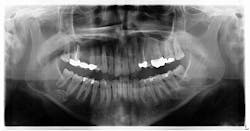

The patient was referred to an oral surgeon for removal of her wisdom teeth. Furthermore, it was requested that the lesion be assessed for a more definitive diagnosis, even though visibly it had not changed in shape, size, or location.

A cone beam scan was taken, and it was noted that there was no lesion within the bone of the mandible. More than likely it was a cast ghost image from a hyoid bone that sat higher than normal. As there were no complaints of neurosensory changes, bony expansion, tenderness to the area, or changes between the two radiographs, there were no treatment recommendations at this time. The area, of course, would be monitored in future radiographs for any clinical symptoms.